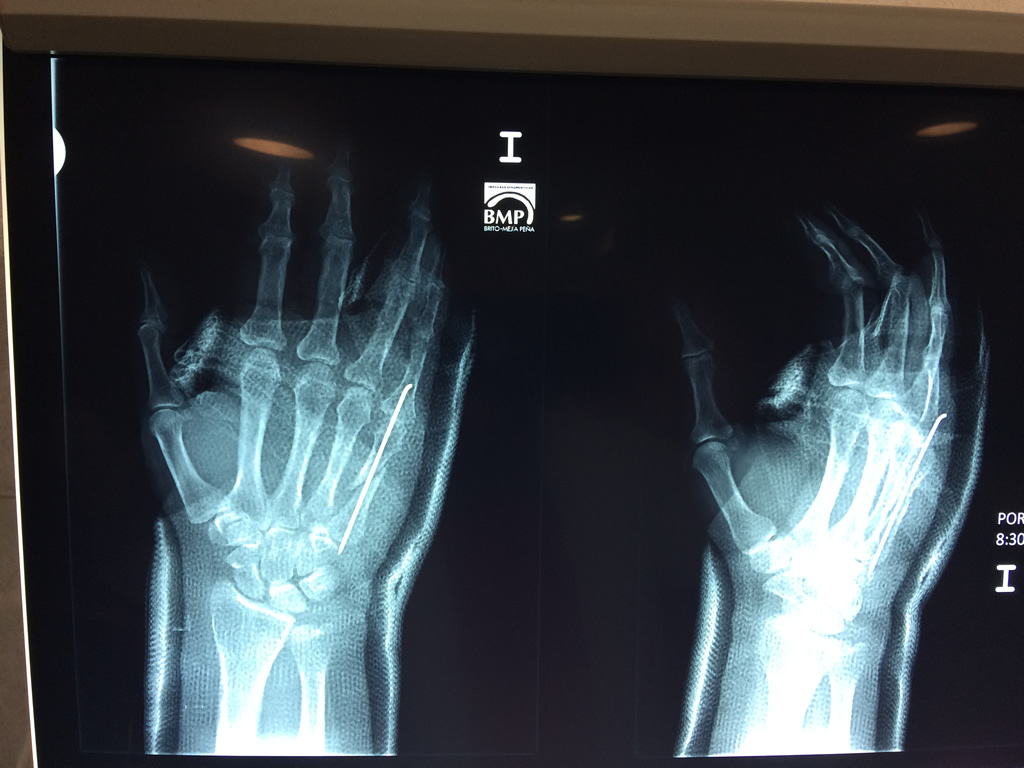

Cirugías de Codo - Cirugías de Muñecas y Manos

Los procedimientos más comunes en cirugía de la mano son aquellos destinados a reparar traumatismos, incluyendo lesiones de tendones, nervios, vasos sanguíneos, y articulaciones; huesos fracturados; y quemaduras, cortes, y otros daños de la piel.